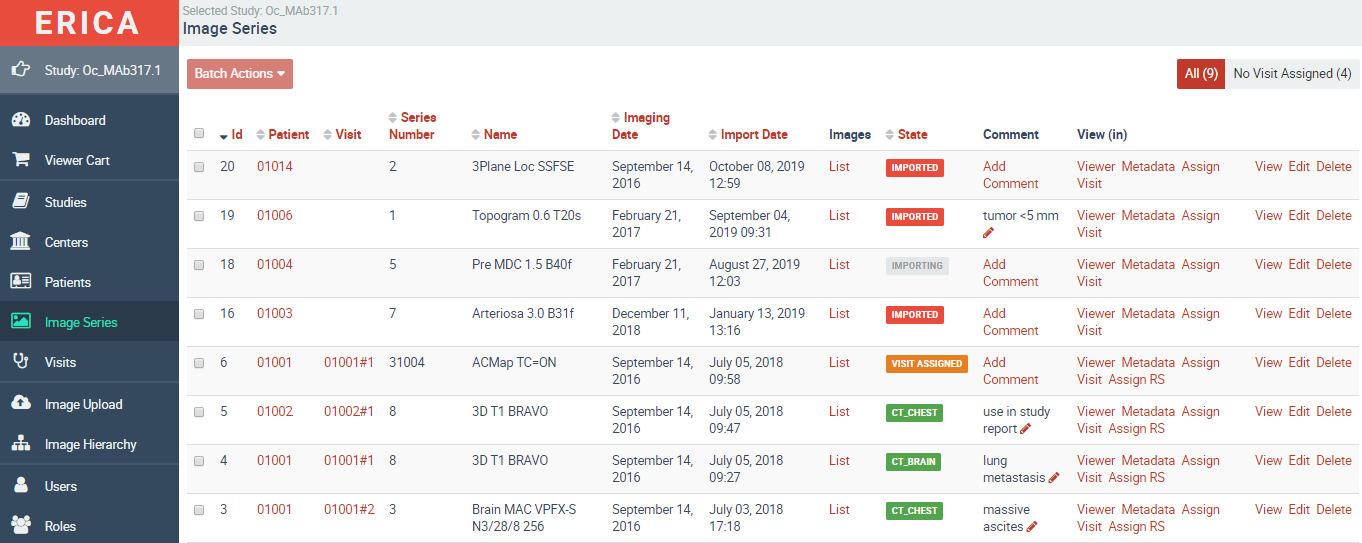

ERICA is our proprietary, fully validated imaging platform — purpose-built for the demands of clinical trials. It covers DICOM image storage, technical and medical quality control, and independent blinded reads in a single, regulatory-compliant environment.

Every project-specific configuration is separately validated. No general-purpose software adapted for clinical use — a system designed from the ground up for this work.